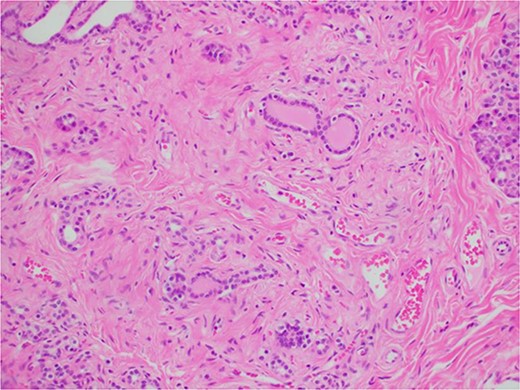

During a thorough inspection of the small bowel in its entirety, a yellow, lobulated oblong lump on the serosa of proximal jejunum was found (Fig. 1). A segment of small bowel including the lesion was resected and sent for histology. The small bowel was re-joined with a stapled anastomosis. Histopathological examination of the lesion revealed a 16 × 13 mm white, serosal nodularity (Fig. 1a). The underlying jejunal mucosa was normal (Fig. 2a). Histological sections were consistent with ectopic pancreatic tissue; they exhibited numerous acinar type glands associated with occasional islet of Langerhans, centred around a main pancreatic duct (Fig. 3). Some of the acinar units show gland drop out, fibrosis, atrophy, and scattered chronic inflammation, indicative of past and chronic pancreatitis (Fig. 4). Microscopically, the EP involved the submucosa and was abutting the serosa. No malignancy was present.

Microscopic histological image showing pancreatic atrophy and fibrosis with scattered chronic inflammation, indicative of past pancreatitis.